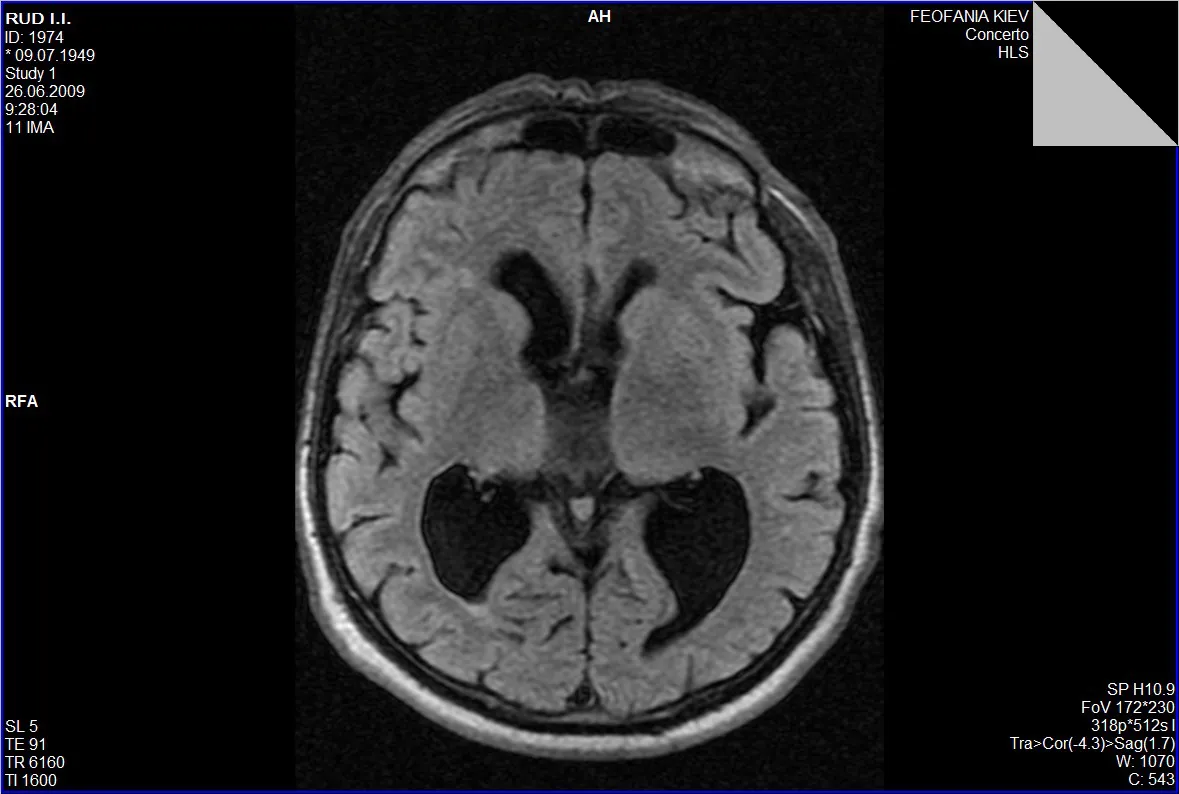

Гідроцефалія, або водянка головного мозку, — це патологічний стан, який характеризується накопиченням цереброспінальної рідини (ліквору) у шлуночках мозку та міжоболонкових просторах.

Запідозрити гідроцефалію можна на підставі виявлення скарг на головний біль, запаморочення, нудоту, порушення зору, порушення координації руху кінцівок, зниження пам’яті, уваги та інших когнітивних здатностей, порушення функції тазових органів (нетримання сечі).

Звернутися з метою обстеження та верифікації діагнозу гідроцефалії із наступним нейрохірургічним втручанням ви можете Центрі Нейрохірургії «Оберіг». До переліку обстежень входить стандартний лабораторний пакет загальноклінічних аналізів та МРТ головного мозку.